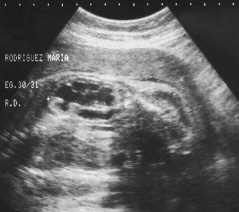

Edad

: 25 Sexo: Femenino

Descripción de las Imágenes y Diagnóstico:

Gesta de 30 semanas (G2 PN2 S-P) se observa HIDRONEFROSIS fetal (Riñón derecho). Líquido Amniótico normal.

Comentario referente al caso:

La dilatación del tracto urinario superior puede ser no obstructiva. Uni o bilateral: Obstrucción de la unión pieloureteral 43%; obstrucción de la unión vesicoureteral 20%; reflujo vesicoureteral 15%; duplicación del colector 12% ; válvula de uretra posterior 10%. La hidronefrosis es la anomalía más frecuente diagnosticada prenatalmente, este objetivo tiende a definir los criterios que la relacionan con la función renal posnatal o con la necesidad de cirugía. La medida más utilizada es el diámetro anteroposterior pélvico intrarrenal en el plano transversal antes de las 20 semanas < a 4 mm, mayor de 20 semanas < a 10 ® una pelvis de 5 a 9 mm probablemente puede ser fisiológica. En las observaciones sucesivas puede observarse: progresión, regresión o ningún cambio. El aumento de la dilatación y la disminución del parenquine supone progresión y si esta última es menor a 5 mm se debe buscar una solución urgente.